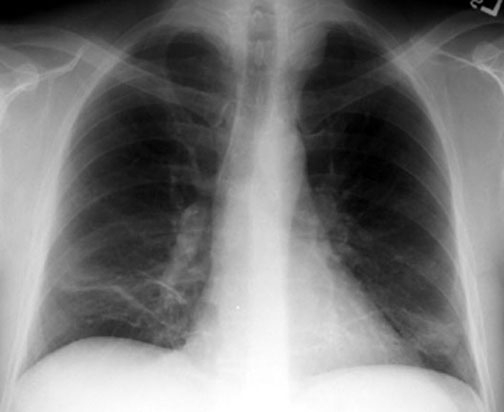

Posterior Mediastinal Mass

- Mass density in left para tracheal region

- Extrapleural

Additional finding include:

• Sub-segmental atelectasis

Sub segmental atelectasis

Plat-like atelectasis